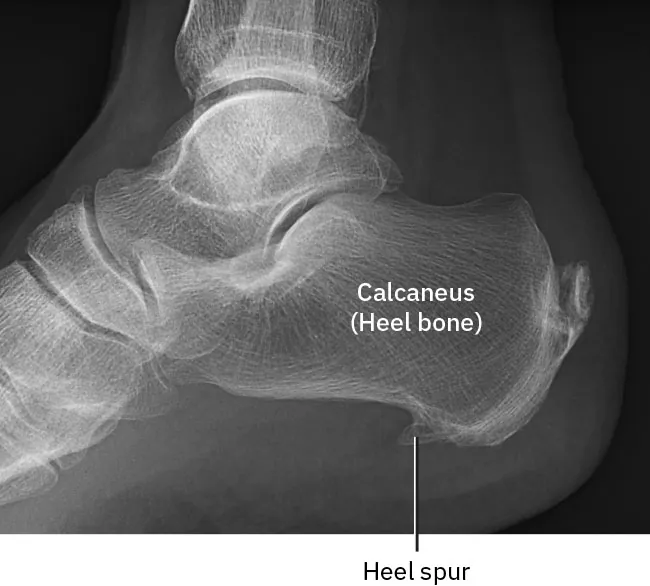

Diagram showing osteoarthritis of the hip joint

Figure 13.6 Osteoarthritis of the hip joint involves the wearing down of the joint cartilage over time, causing pain. (credit: Hip Osteoarthritis by Injurymap/Wikimedia Commons, CC BY 4.0)